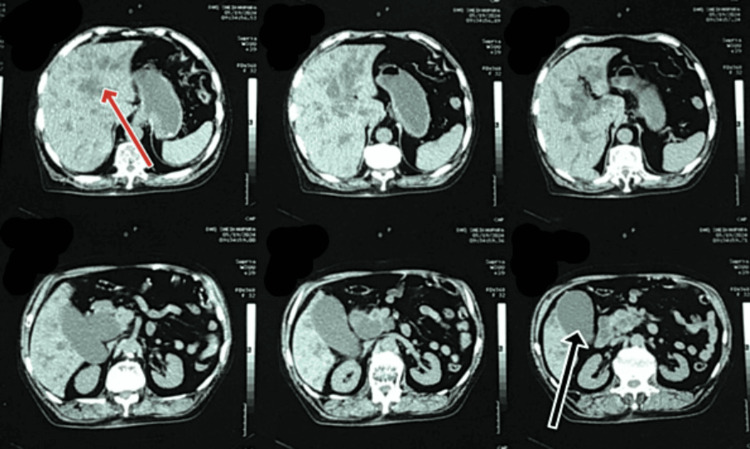

These findings indicated an inflammatory and obstructive process within the biliary system. An abdominal ultrasound revealed a normal-sized liver (13.4 cm) with a normal parenchymal structure, a dilated portal vein (18 mm), and a mildly distended gallbladder (GB) full of sludge. Figure 1 shows the radiologic image of the non-contrast abdominal and pelvic CT scan, which indicated abrupt narrowing of the distal CBD, resulting in moderate dilation of the CBD lumen proximal to the intrahepatic biliary channels (IHBCs) and significant distension of the GB lumen.